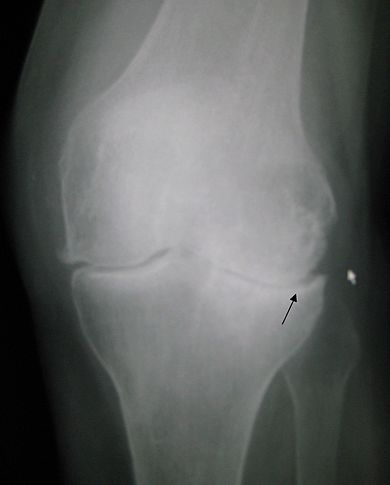

L’arthrose du genou

J’ai regardé mon agenda…ma douleur du genou droit est intervenue le 9 juillet lors de la montée au Vieil Armand. Une douleur inhabituelle pour moi qui n’ai jamais rien connu de tel.

Depuis les deux genoux se sont mis de la partie, et aussi les doigts (mais j’avais déjà des signes précédemment) et aussi le pied droit. J’ai consulté les nombreuses pages du net. La pharmacopée est classique. Elle passe par les anti-inflammatoires, puis la chirurgie. Mais le mieux, à mon avis, est encore de prendre son mal en patience avant de recourir à la méthode forte.

Des montées et descentes d’escalier douloureuses qui cependant n’empêchent pas de faire du vélo. Une légère souffrance au pédalage et c’est tout. On y pense et on évite de trop presser sur les pédales. D’ailleurs le vélo n’est pas déconseillé. Contrairement à la course à pied.